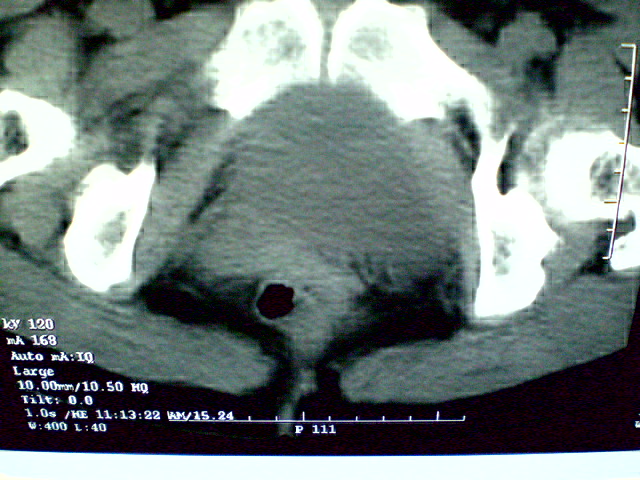

f 60y,b超提示脂肪瘤.[img][/img]

右侧附件囊性畸胎瘤,三种组织均见.

那个高密度灶形状好象牙齿。典型,收藏了

脂肪密度肿块,内可见团块状影,典型皮样囊肿

的确比较典型的畸胎瘤!不过,应该确切的说是盆腔畸胎瘤,右侧附件来源的可能性比较大。

有钙化,畸胎瘤